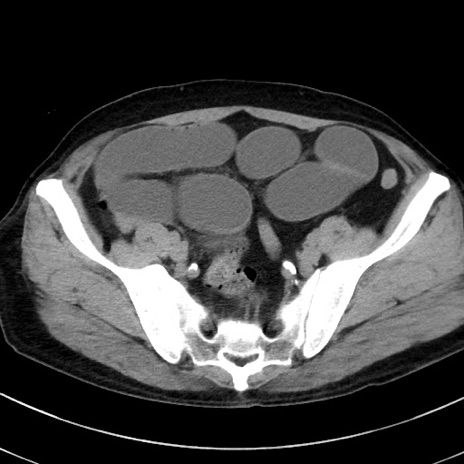

冠状断像

【症例】70歳代 男性

【主訴】腹痛・嘔吐

【現病歴】昨晩より、嘔吐・腹痛あり。今朝になっても嘔吐あり。来院。

【既往歴】心臓バイパス手術、開腹胆摘、腸閉塞

【身体所見】BP 107/71mmHg、HR 116/min、腹部:平坦、軟、下腹部に軽度圧痛あり。反跳痛なし。

【データ】WBC 15100、CRP 0.32